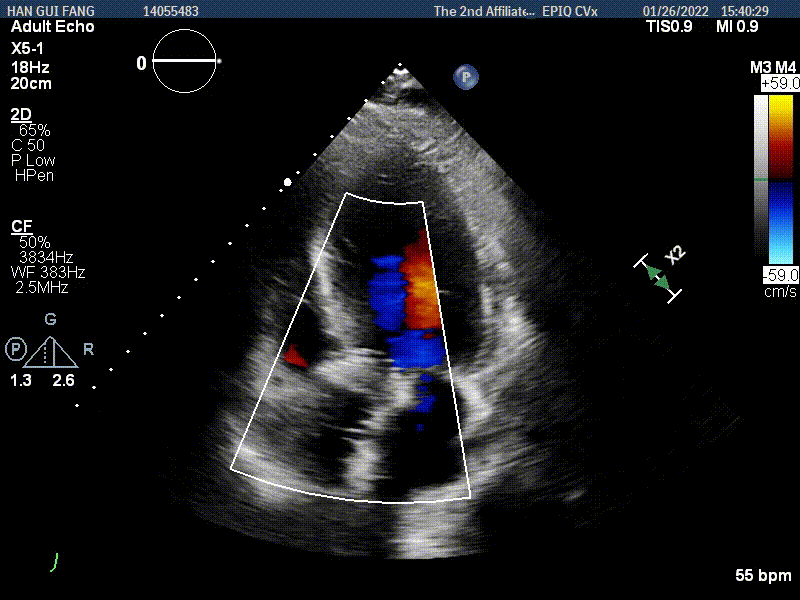

手术使用Z-Med 20mm球囊预扩两次,植入AV23 TaurusNXT主动脉瓣,Snare圈套器协助输送系统过弓、过瓣,120次/分起搏频率下,在左右重合位影像下释放瓣膜达到工作位,造影显示位置偏深,完全回收两次后释放达工作位,造影显示位置仍然不理想,之后第三次使用部分回收,精准释放瓣膜,之后使用Z-Med 20mm球囊后扩张两次。术后即刻超声心动图评估显示瓣膜位置良好,微量瓣周漏,主动脉瓣口峰值流速为1.90m/s,平均跨瓣压差为8mmHg,有效瓣口面积 1.60cm²,血流动力学指标理想。

超声影像